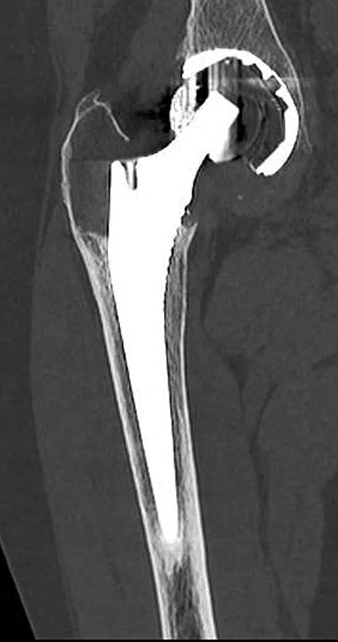

of the femoral head compared to the 2013 postoperative images (Figure 2). Wear measurements were obtained by adapting the method of Charnley et al. [4] used for polyethylene bearings, as no validated score exists for ceramic wear measurement on radiographs. CT confirmed cranial migration of the femoral head without clear fracture of the ceramic liner or head, and revealed femoral and acetabular periprosthetic granuloma (Figure 3).

Figure 3: Coronal CT scan of the right hip, 2024.

Given the disabling pain and probable implant wear, a one-stage acetabular component and femoral head revision was indicated and performed in July 2024.